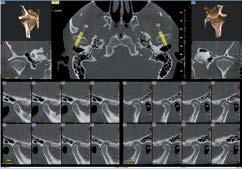

Nell’ambito della radiologia 3D ortopedica, il centro diagnostico utilizza il nuovissimo macchinario NewTom 5G XL, in grado di individuare con la massima precisione la presenza di fratture o lussazioni delle articolazioni, controllare la corretta guarigione di una frattura, valutare una lesione o una ferita causata da infezione, artrite o crescita anormale dell’osso.

Il tutto mediante una semplice e veloce scansione, grazie alla quale si otterranno diverse immagini in 3D ad altissima risoluzione e, per ottenere immagini ancora più nitide mediante un bassissimo dosaggio di radiazioni, gli esperti si avvalgono dell’innovazione racchiusa nella tecnologia Cone Beam.

Se con la radiologia tradizionale era necessario eseguire scansioni multiple, la novità introdotta dal macchinario NewTom 5G XL risiede nella capacità di fornire immagini ad alta risoluzione in un’unica scansione, mostrando nitidamente i dettagli delle articolazioni degli arti superiori e inferiori. Inoltre, a differenza della tecnologia 2D, la radiologia 3D ortopedica permette di individuare immediatamente alcune patologie come quella del metatarso, la quale richiede un allineamento visivo dedicato o una diagnosi delle micro fratture ossee.